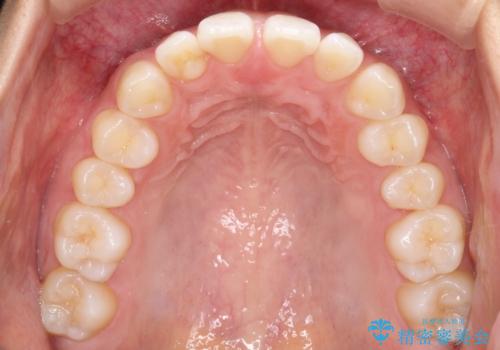

すきっ歯のインビザラインによる目立たない矯正

- すきっ歯を治したいとのことで来院されました。

上下ともに前歯に隙間がありました。

目立たない装置をご希望のためインビザラインで矯正治療を行うこととしました。

使用時間を守っていただけたので、スムーズに治療を終わることができました。